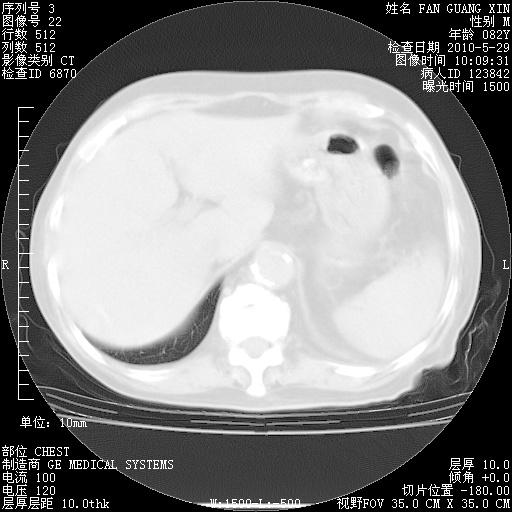

再治疗10天后的肺部CT

再治疗10天后的肺部CT 纵膈窗

阅读此次胸部CT,肺间质渗出性改变较入院时有吸收。目前从体温、白细胞、中性分叶明显增高,肯定存在细菌感染(发生医院感染哦,若无消化道及泌尿系统等感染的依据,肺部感染可能大)。若你院头孢哌酮舒巴坦钠耐药率较高,同意你的方案,若48小时体温仍高,可考虑使用碳青霉稀类抗菌药物,同时可予超声雾化、注意滴数时加大液体量。白蛋白33.30g/L较低哦,需加强营养等支持治疗。